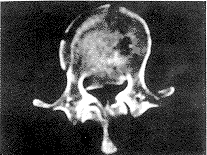

, http://www.100md.com 3.2.1 骨折椎平面 间接减压效果T12、L1骨折优于L2骨折。这可能与T12、 L1正常生理状态下有轻度后凸,在恢复脊柱前凸过程中,后纵韧带及椎间盘纤维环张力较大,使骨块复位应力增强,而L2是后凸与腰椎前凸过渡椎,纵向韧带张应力增大不明显有关。根据间接复位能力不同这一特点,后期我们对L2骨折术前存在严重椎管入侵(>50%)者,在实施复位固定同时,作经椎弓根侧前方减压,使术后椎管腔达到足够的减压范围,见图1~3。

图3 L2爆裂型骨折术前、术后CT片